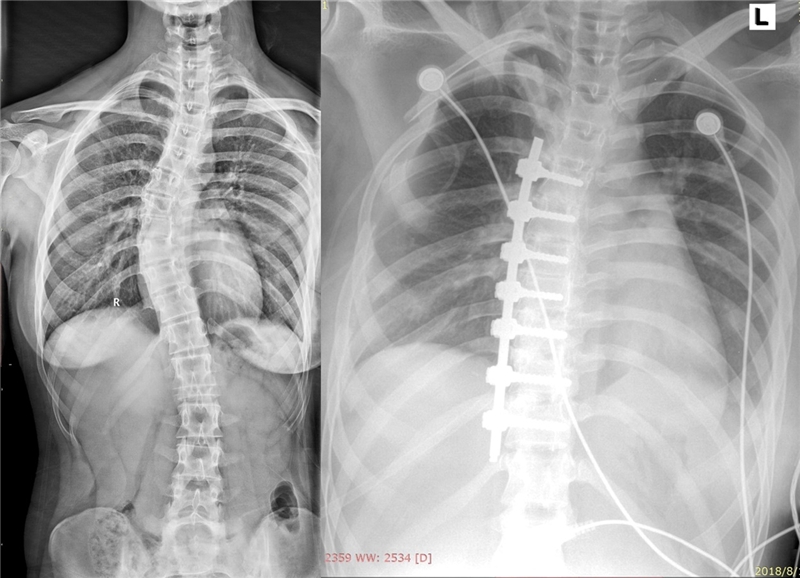

患者术前术后X线对比